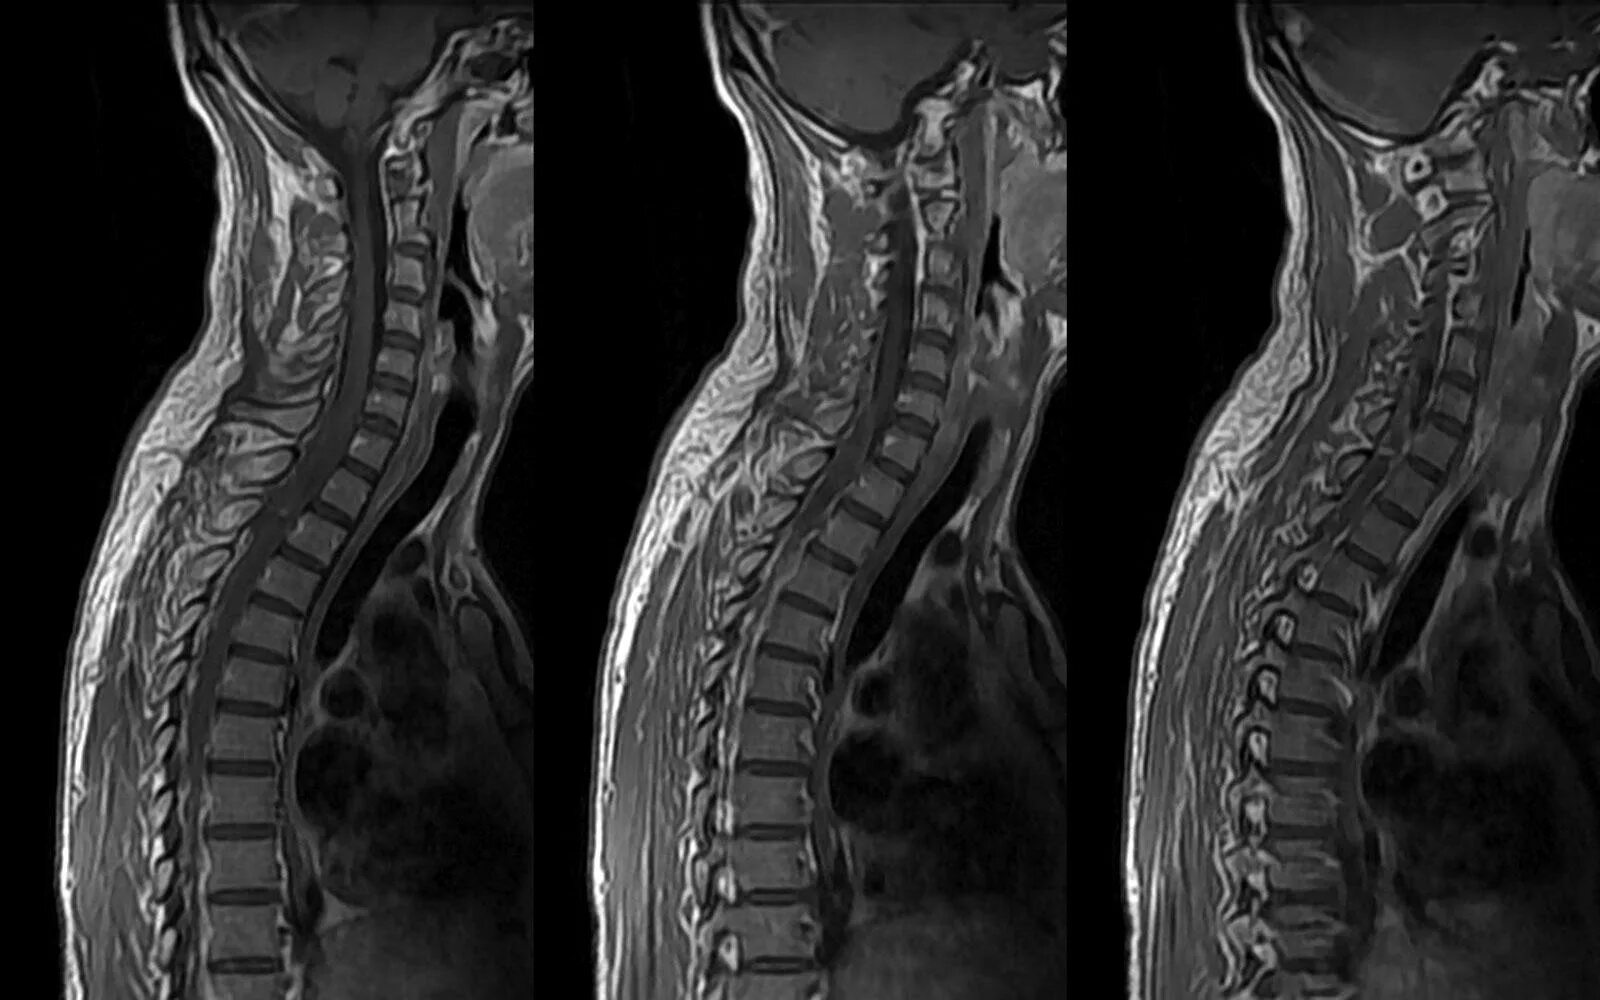

Мрт шейно поясничного отдела